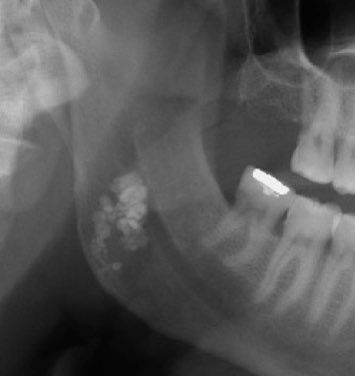

وبالنسبة لاورام الفكين الحميدة حنتكلم عن ٣ أنواع منها:

Odontoma

Ameloblastoma

Adenomatoid odontogenic tumor

الغالبية من الحالات لا Ameloblastoma تظهر كتمدد في عظام الفك على هيئة مجموعة تكيسات متصلة وفي قليل من الحالات تظهر ككيس واحد متمدد داخل الفك والتشخيص يعتمد على نتيجة الخزعة (العينة)